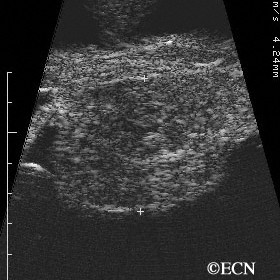

Choroidal Hemangioma

Choroidal Hemangioma - Moderately high internal reflectivity and a "dome" shape are typically revealed by ultrasound imaging of choroidal hemangioma.